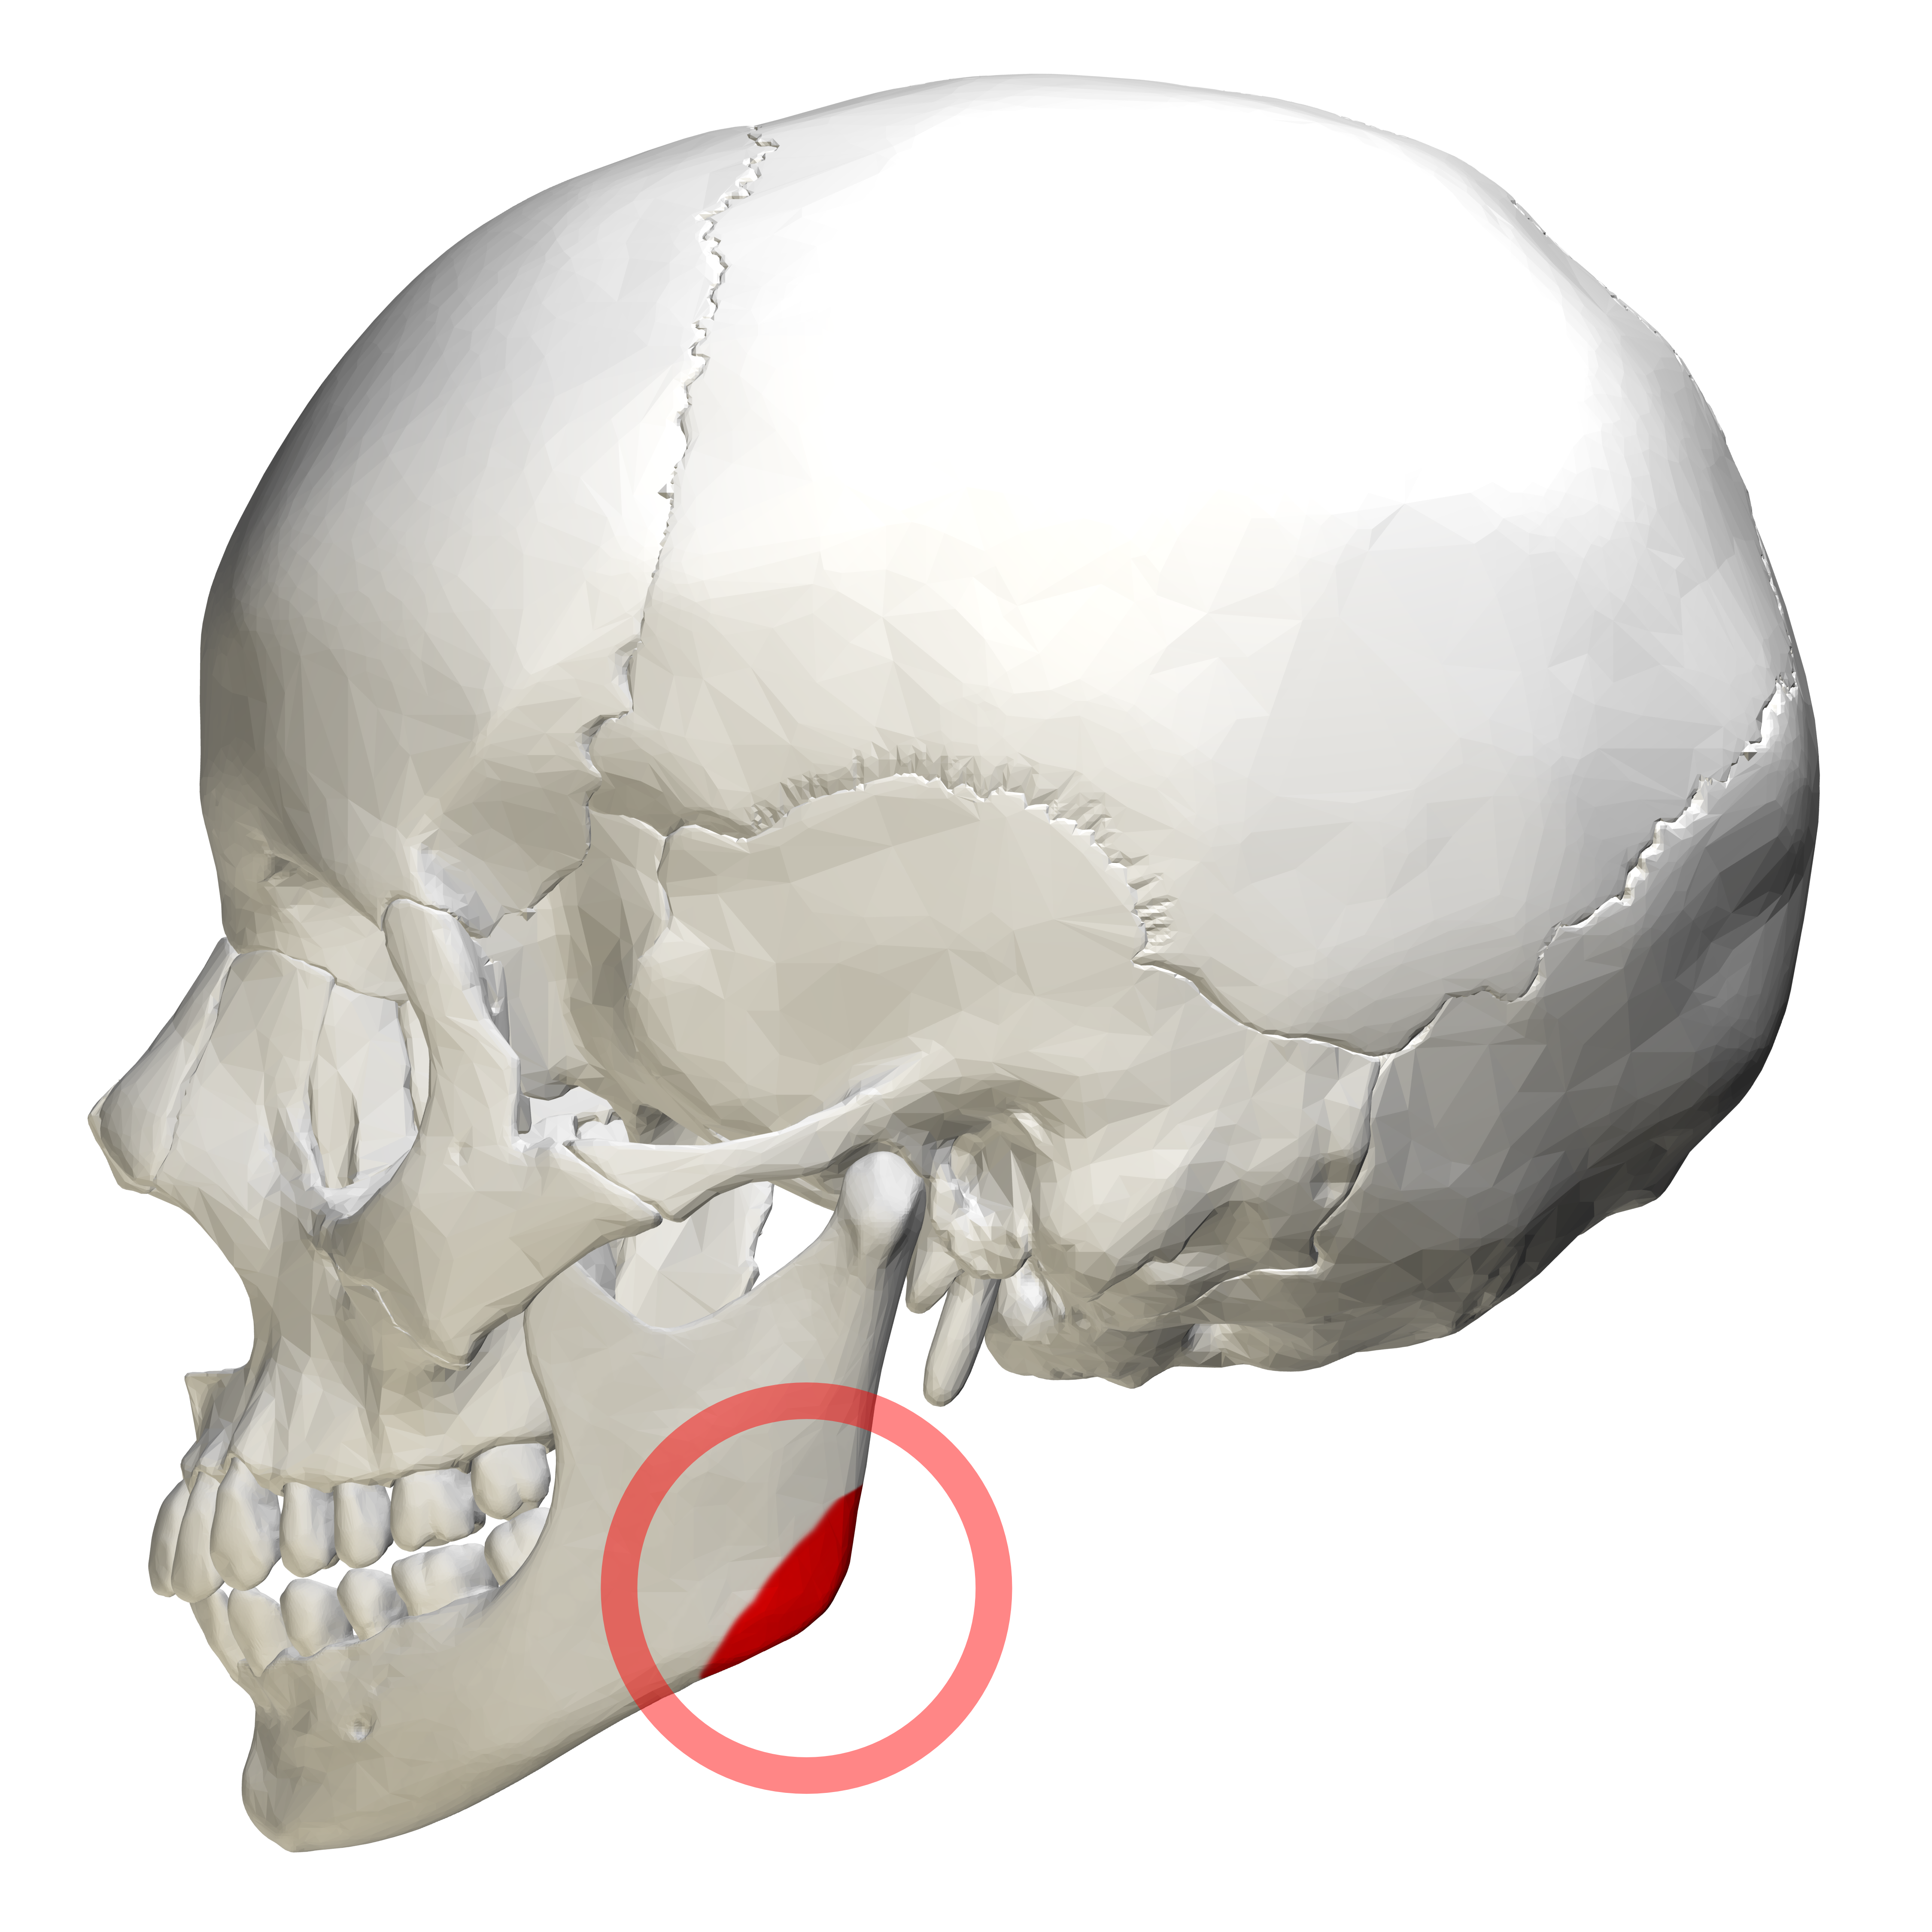

what are the bony landmarks of the mandible and surrounding structures

mandibular condyle

coronoid notch

coronoid process

mandibular foramen

lingula

mental foramen

mental ridge

mental fossa

lingual foramen

genial tubercles

inferior border of the mandible

mylohyoid ridge

external oblique ridge

angle of the mandible